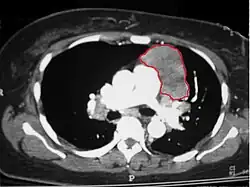

В группу опухолей средостения входят новообразования различной структуры и злокачественности, находящиеся в анатомических пределах средостения и имеющих внеорганное происхождение. К новообразованиям заднего средостения относятся лимфомы, тимомы и метастатические карциномы.

В число объёмных образований переднего средостения входят тимома, лимфома, феохромоцитома и дизэмбриогенетические опухоли (тератома и др.). Объёмные образования переднего средостения имеют более высокий риск злокачественности, чем объёмные образования других локализаций.[1][2]

Тимомы наблюдаются в любом возрасте, чаще в 30—40 лет. Наиболее часто встречающаяся первичная опухоль средостения (20 %). Различают лимфоидные, эпителиальные, веретеноклеточные или смешанные тимомы. Злокачественная форма, отличающаяся высокой инвазивностью в окружающие ткани, встречается почти так же часто, как и доброкачественная (35—50 % больных). Характерно распространение тимомы по плевре, при этом гематогенные и лимфогенные метастазы редки. Тимома выявляется у 15 % пациентов с миастенией, при этом миастения выявляется у 50 % пациентов с тимомой. Описаны случаи тимом заднего средостения.